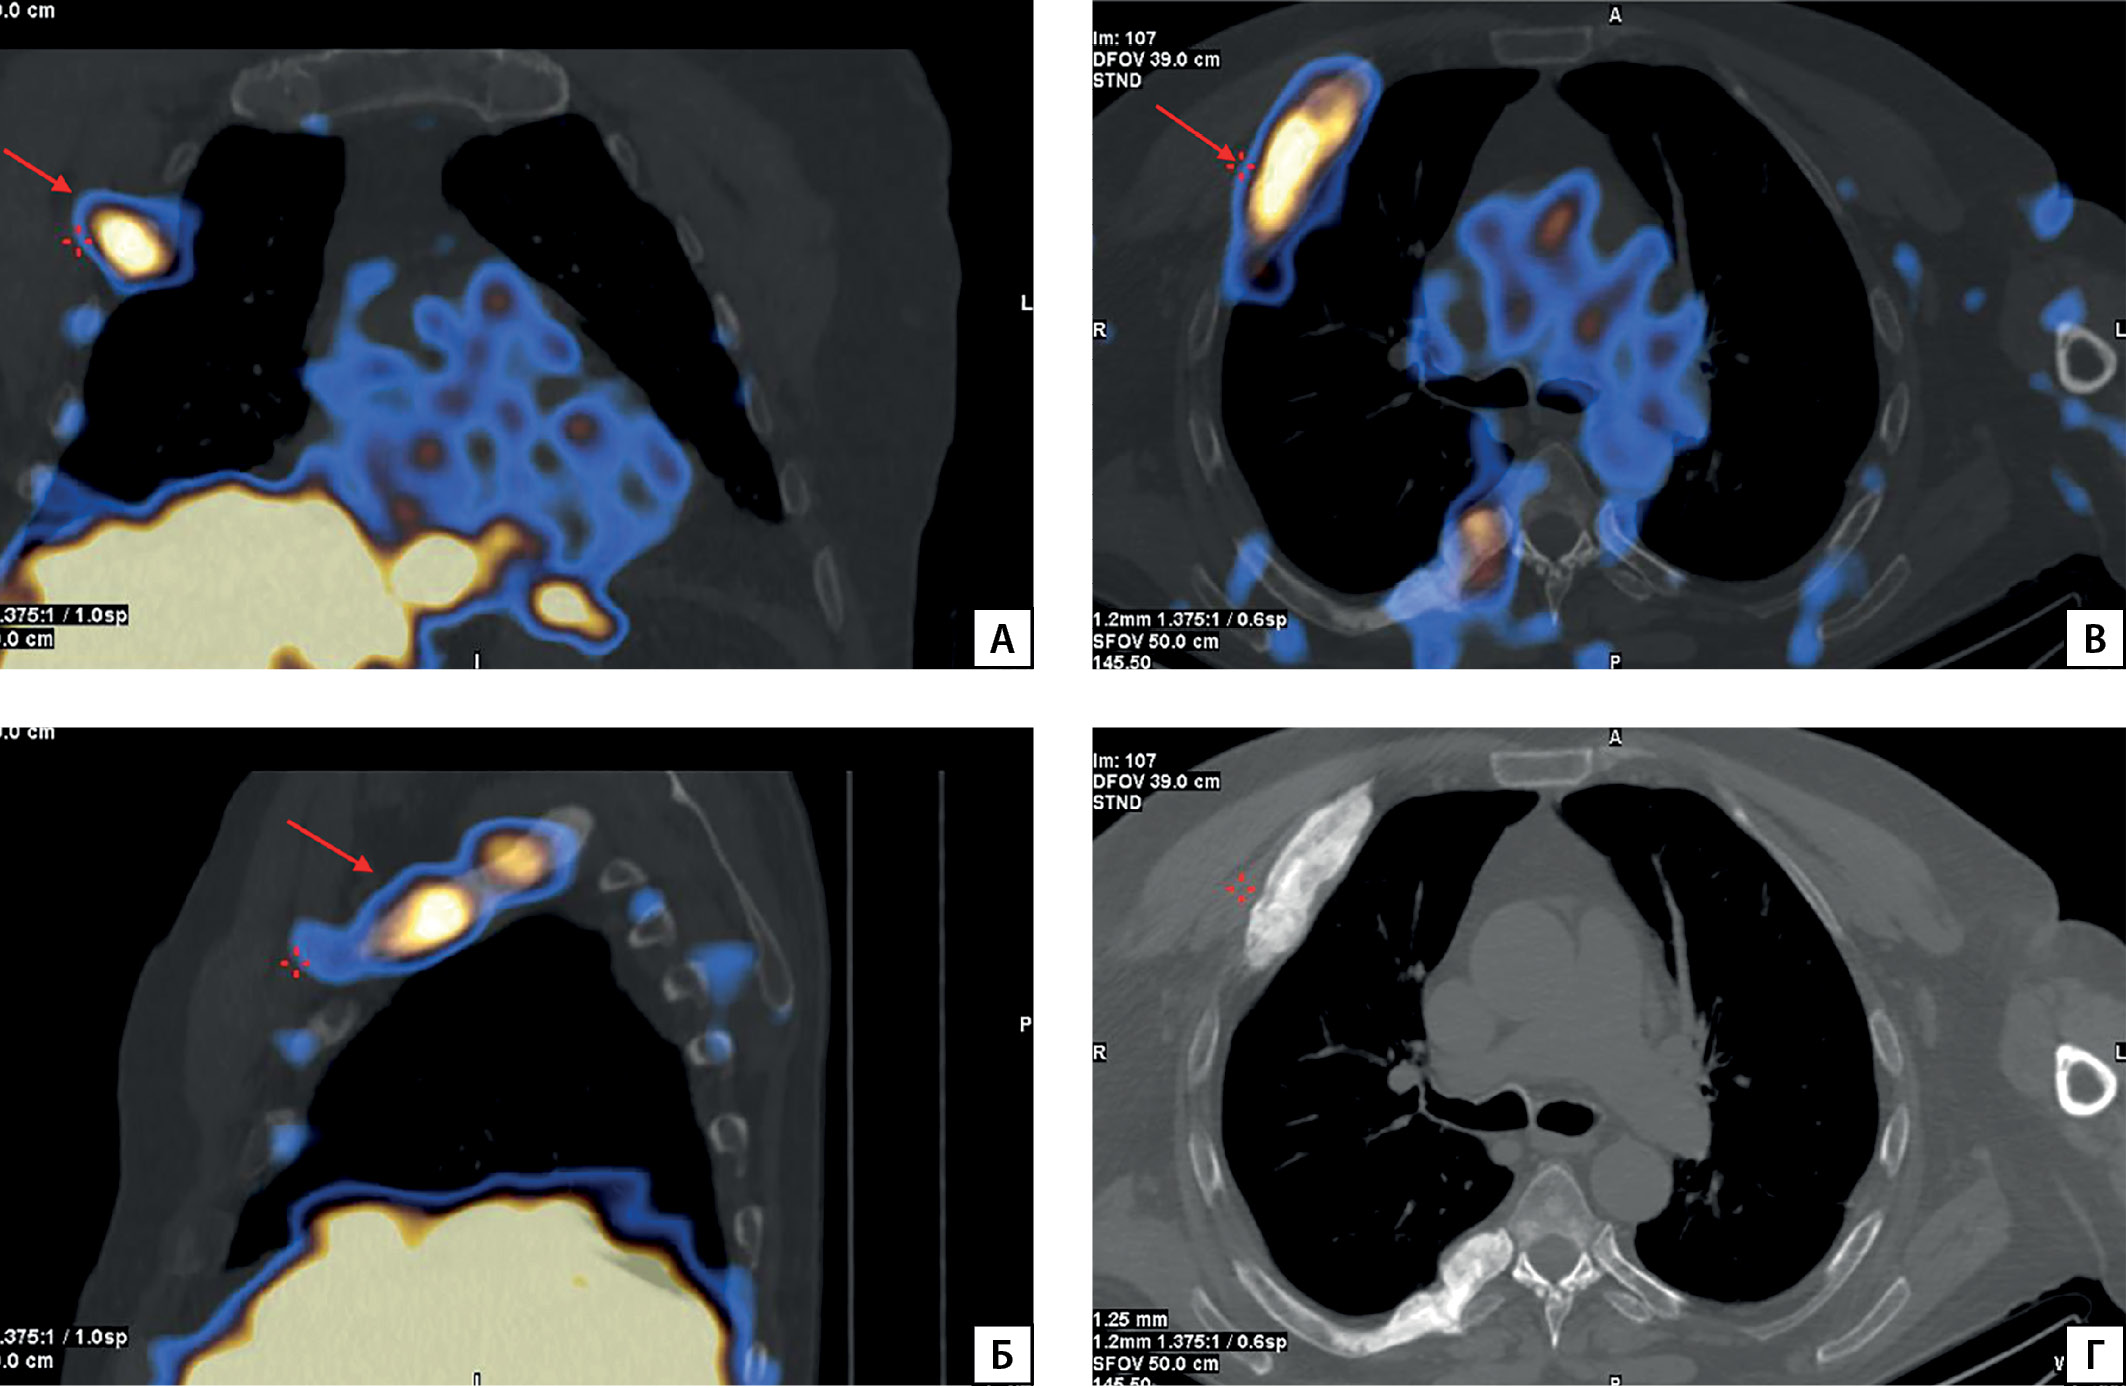

Рисунок 2. МСКТ костей таза

Описание: А) в головках и шейках бедренных костей зоны остеосклероза без четких контуров, с наличием патологического перелома шейки правой бедренной кости (стрелка); Б) очаги остеосклероза в правых лонной и седалищной костях с формированием патологического перелома (стрелка) и остеобластическая перестройка левой седалищной кости

При осмотре в отделении: рост 172 см (снижение в росте на 10 см за жизнь), масса тела 85 кг, индекс массы тела 28,7 кг/м2. В ходе расширенного лабораторного обследования в стационаре сохранялись гипофосфатемия в сочетании со сниженным индексом тубулярной реабсорбции фосфатов, повышение уровня ЩФ (табл. 1). По результатам МСКТ — патологические переломы 4–10-го ребер справа и 5–9-го ребер слева в стадии консолидации, множественные застарелые компрессионные переломы тел Th2–8, Th10, Th12, L1–3, L5, смешанная перестройка правых лонной и седалищной кости с формированием патологического перелома и остеобластическая перестройка левой седалищной кости, более соответствующие вторичным изменениям (mts), однако нельзя полностью исключить изменения, являющиеся следствием опухоль-индуцированной остеомаляции, изменения 3, 6-го ребер справа более соответствуют фиброзной дисплазии или опухоль-индуцированной остеомаляции (рис. 1, 2). На основании данных анамнеза, лабораторных и инструментальных исследований установлен диагноз «фосфопеническая форма остеомаляции опухолевого генеза», инициирована терапия препаратами фосфора и увеличена доза альфакальцидола до 4 мкг. На фоне проводимой терапии отмечалось повышение уровня фосфора с 0,38 до 0,48 ммоль/л, снижение активности ЩФ, пациент субъективно отметил уменьшение выраженности болей в костях.